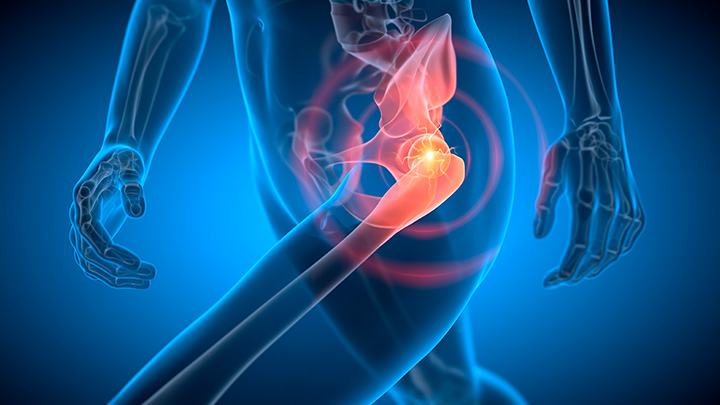

A artroplastia é hoje a principal proposta terapêutica para o tratamento das dores e lesões degenerativas avançadas de quadril. O Hospital Moriah prioriza as cirurgias realizadas por técnicas minimamente invasivas, que visam favorecer a diminuição do tempo de internação hospitalar e dor no pós-operatório, além de reintegrar os pacientes a sua rotina normal em aproximadamente 30 dias.

Nesta abordagem, a incisão é feita longitudinalmente na parte frontal, não há o corte dos músculos e os nervos são preservados. Isso reduz o risco de lesões nos músculos, tendões, vasos e nervos.